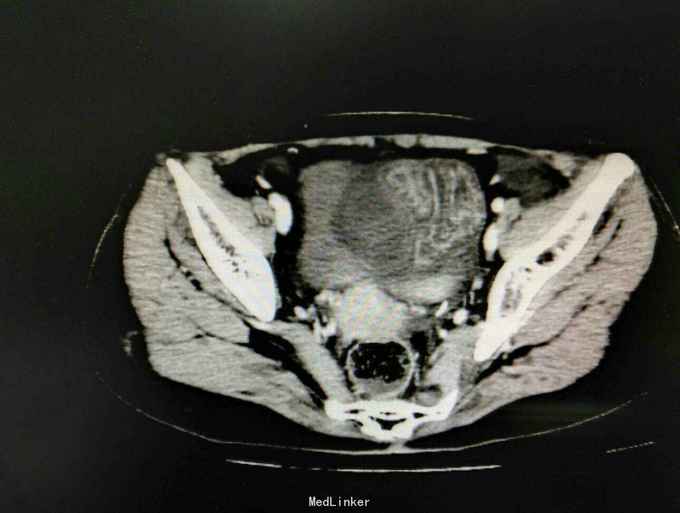

入院后急查血象稍高,完善急诊CT示内疝并闭袢性肠梗阻,予急诊行剖腹探查,术中见子宫右移,距离回盲部50cm回肠内疝入子宫与前腹壁所形成的黏连中,松解黏连,见回肠约15cm缺血坏死,予切除后吻合,缝闭黏连所造成的腔隙,关腹。术后常规治疗,患者回复可予出院。病理如图。

患者腹痛入院,各项生命体征平稳,无腹膜炎体征,抽血也没较大的异常,常规来说并不需要特殊处理,所幸的是完善了CT,及时发现了腹痛原因,因黏连形成的腔隙与腹腔隔离,所以患者腹痛不明显,即使肠坏死一般情况也无特殊,患者发病时间短,CT检查及时,避免了延误治疗导致肠坏死加剧。从中我们可以吸取教训,对于急腹症腹痛不典型的患者,不能用某种炎症解释病情的话,如果既往有手术病史,一定要注意内疝可能,对当前的医疗环境来说,急诊CT可以帮助明确诊断